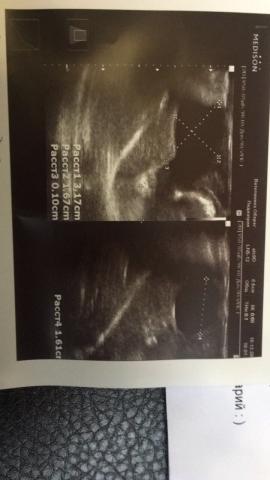

Если можно, то немного подробнее. На основании чего вам поставили такой диагноз, только на основании проведенного УЗИ? Может быть, собаке брали какие-то анализы? Если да, то выложите, пожалуйста, здесь их результаты. Если только данные УЗИ, то это разговор ни о чем (я имею ввиду панкреатит). Гастрит по данным УЗИ вообще не ставят.

Поставили диагноз на основании УЗИ , а до этого сдавали кровь

К сожалению, ничего не могу рассмотреть. Попробуйте сами прочесть описание с фото. Если сможете, сделайте снимок более качественным. Или можно снять крупнее по частям. Может быть, тогда буквы будут видны более четко.

Спасибо, фотографии четкие. Я все прочитал. Как я и думал, там и "не пахнет" никаким гастродуоденитом, а тем более, панкреатитом.